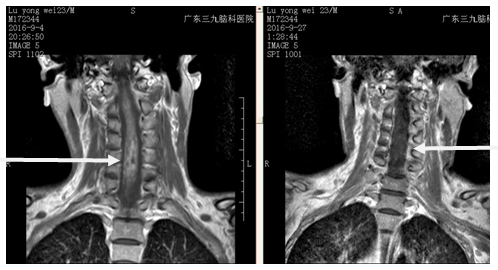

陆某某,男性,23岁,于2015年4月无明显诱因出现颈部疼痛,外院行MRI检查示:颈髓内占位,考虑肿瘤或炎症,给予保守治疗效果不明显,疼痛症状持续存在1年且逐渐加重,为求进一步治疗,来我院就诊。入院后完善检查后诊断为:延髓、颈髓内多发占位性病变。患者入院时病情危重,急行延髓,脊髓内胶质瘤切除术。手术由神经外二科主任林涛主刀完成,术后予以同时予脱水、预防感染、预防癫痫、康复训练、营养脑神经及营养支持等对症支持治疗。患者身体状况较好出院。

脊髓胶质瘤治疗以手术为主,辅以放疗或化疗。目前的观点趋向于肿瘤中等大小,神经系统功能部分障碍时手术为宜,此时肿瘤相对容易暴露,术后神经系统功能有可能恢复。上述患者入院时伴有多种并发症,情况较重,手术指针明确。术后对症给予综合治疗,减少了术后并发症的发生。本案例术中铣刀锯开2-6椎板,咬骨钳咬除枕大孔后缘及寰椎椎板骨质,游离骨瓣大小约12cm*5cm,上至枕大孔上方3cm,下至第七颈椎上缘,激光刀沿脊髓背侧中线纵形切开,上至延髓,下至第6颈髓下缘,可见约0.3cm灰褐色肿瘤组织,随后显微镜下全切肿瘤。